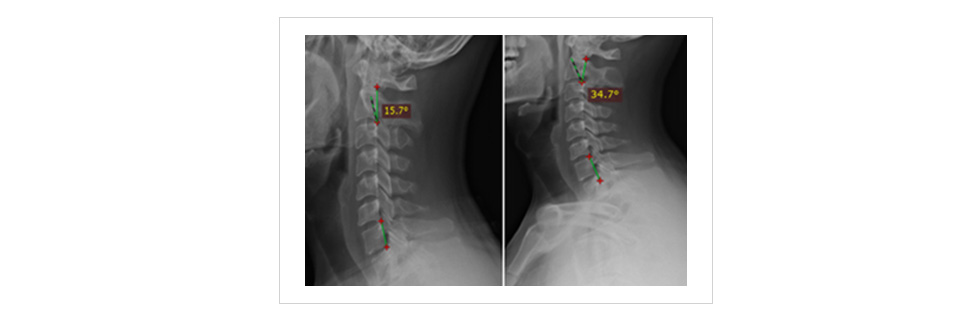

患者,男,33岁,治疗前双侧肩胛内缘及后颈部肌肉僵硬、酸麻、疼痛,以右侧为重,右侧上肢麻木,颈椎活动明显受限,查体示:椎孔外神经卡压(+),颈椎曲度15.7°。

使用6个月后复查,结果显示,颈肩部功能受限程度明显改善,疼痛评分降低,各查体试验阳性体征减弱,颈椎曲度逐渐恢复为34.7°,对疗效满意。